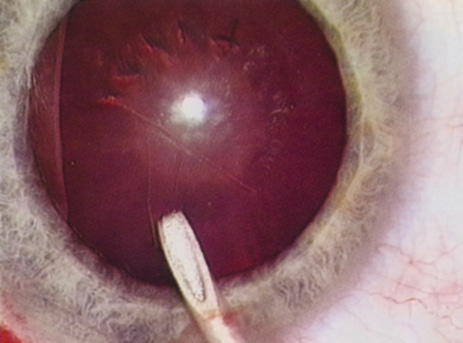

Although slit-lamp examination can give the ophthalmologist an excellent estimate of endothelial health, sometimes a formal assessment of the corneal endothelial cell density is helpful (Fig. 4). This information is most likely to be helpful in advising patients who may be at greater risk of postoperative corneal decompensation. Specifically, patients with cornea guttata, previous ocular surgery, history of blunt ocular injury,56 exfoliation syndrome,57 iridocorneal-endothelial syndromes,58 or a history of glaucoma59 are known to have reduced endothelial cell counts. Patients with a history of acute angle closure are at particular risk because each episode of elevated intraocular pressure can damage endothelial cells.60

There are qualitative and quantitative methods for endothelial cell evaluation. Cell density can be measured directly with an endothelial cell camera. The surgeon also should view the photograph and qualitatively estimate the regularity of the endothelial cell mosaic. Some instruments calculate a coefficient of variability and percent of hexagonal cells.

When an endothelial cell camera is not available, qualitative assessment of count and cell morphology can be accomplished at the slit-lamp using a technique called specular reflection.61 The ophthalmologist focuses a narrow parallelepiped on the corneal epithelium, directing the beam at the periapical cornea from a 45-degree angle. The slit beam is moved slowly from side to side until the bright corneal reflex strikes the examiner's view from the epithelial surface reflection (first Purkinje-Sanson image). On high magnification, the examiner should focus on the endothelial surface just next to the bright reflex. The image of the endothelial mosaic will come into view. The surgeon can make a qualitative assessment of the cell density and degree of regularity. With practice, these estimates can be surprisingly accurate.

The implications of a reduced endothelial cell count are primarily prognostic and can provide the surgeon with more information to help counsel the patient about the risk of corneal decompensation with cataract surgery. Gentle phacoemulsification without triple procedure is recommended when cornea is clear and compact, given that a significant number of patients may be able to avoid a corneal transplant despite uncountable cell densities. However, these patients should be advised that they may be at an increased risk of requiring a corneal transplant.